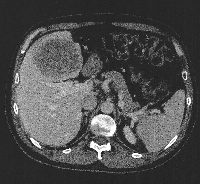

Πρόκειται για άνδρα ασθενή 44 ετών, ο οποίος υποβλήθηκε σε αξονική τομογραφία άνω κοιλίας στα πλαίσια διερεύνησης επιγαστραλγίας. Βρέθηκε μάζα στο 4ο, 5ο και 8ο ηπατικό τμήμα (εικόνα 1). Δε διαπιστώθηκαν σημεία κίρρωσης. Η διερεύνηση για πιθανή πρωτοπαθή εστία εκτός ήπατος ήταν αρνητική. Τέθηκε η διάγνωση της πρωτοπαθούς ηπατικής μάζας (HCC vs CCa). Η εικονική αριστερή εκτεταμμένη ηπατεκτομή με ανάλυση MEVIS (εικόνα 2) οδήγησε σε ηπατικό κολόβωμα μεγέθους 30% του αρχικού, ποσοστό που κρίθηκε ανεπαρκές. Η εικονική κεντρική ηπατεκτομή με ανάλυση MEVIS (εικόνα 3) οδήγησε σε ηπατικό κολόβωμα μεγέθους 65% του αρχικού, ποσοστό που κρίθηκε ικανοποιητικό. Για το λόγο αυτό, ο ασθενής υποβλήθηκε σε κεντρική (parenchymal sparing) ηπατεκτομή (εικόνα 4). Tο παρασκεύασμα αποτελούνταν από τα ηπατικά τμήματα 4b, 5, 8- και τη χοληδόχο κύστη (εικόνα 5). Η διατομή του (εικόνα 6) ανέδειξε μάζα μεγέθους 9 εκατοστών με κάψα, η οποία αφαιρέθηκε άθικτη. Τα ιστολογικά χαρακτηριστικά του όγκου (CK7+, CK19+, CK20-) ήταν συμβατά με CCa (mass forming). Ο ασθενής έλαβε εξιτήριο τη 10η μετεγχειρητική ημέρα.